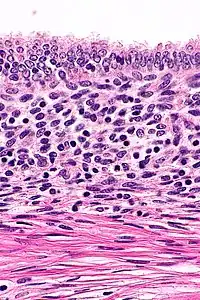

High magnification micrograph of uterine adenomyoma.

Histopathology of uterine adenomyosis. H&E stain.